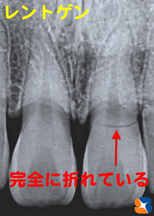

骨折をレントゲンで確認

コラム「骨折をレントゲンで確認」の画像